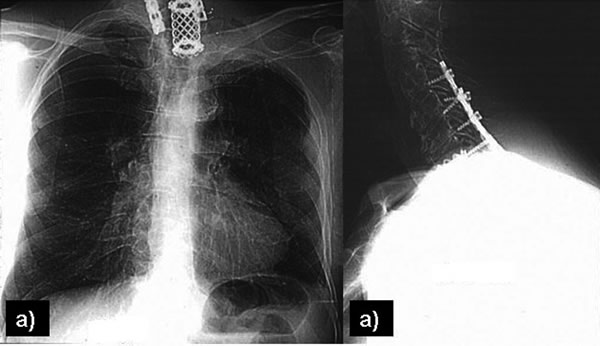

Vertebral body resection

Vertebral body invasion (Figure 17) has traditionally been considered a contraindication for surgical resection in SST. The combined efforts of thoracic surgeons and neurosurgeons specialized in spine stabilization, and recent advances in spinal instrumentation, have led to the development of surgical techniques for resecting vertebral bodies with malignant involvement. As a rule, up to one-quarter of the vertebral body may be removed without affecting the stability of the column. For SST extending into the intervertebral foramina without intraspinal extension, Dartevelle and others [18] described a technique for radical resection that combines the anterior transcervical and posterior midline approaches.

The classic posterior approach can be used to perform a total or partial vertebrectomy and neural foramina or transverse process resection [14, 19]. In patients with neural foramina or transverse process invasion only, the transverse process is drilled out with a high-speed diamond burr power drill, and the nerve roots are ligated and divided. If there is significant involvement of the surrounding osseous structures, a multilevel laminectomy and total or partial vertebrectomy are carried out through a posterior midline extension of the thoracotomy. The vertebrectomy defect may be reconstructed with autologous bone or a prosthesis. Anterior fixation is obtained with placement of an anterior locking plate and screw construct, and posterior fixation using rods fixed with screws and hooks is done with extensive resections and multilevel laminectomies (Figures 18-19). With a radical resection in the case of vertebral involvement, the transverse process and vertebral body must be resected first, before continuing the operation.